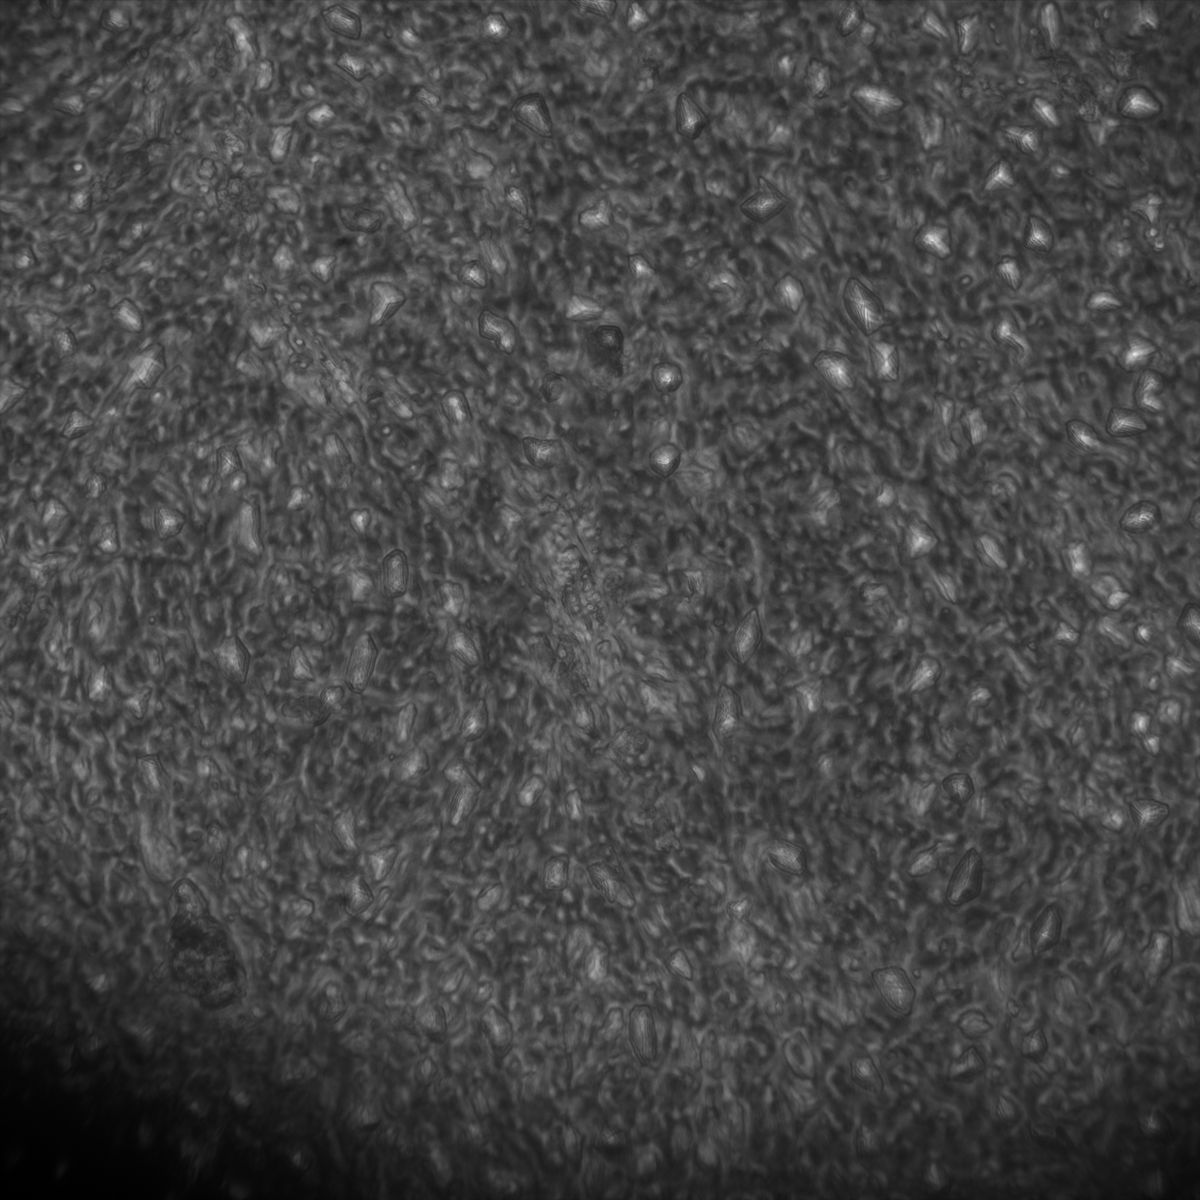

Muscle Cancer